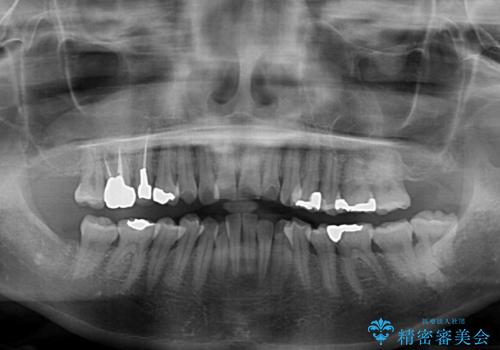

- 前歯のデコボコを気にして来院された患者様です。

上下前歯の先端同士が接触する切端咬合であったため、上顎は歯列を拡大し、下顎はIPR(歯と歯の間を削る)により叢生を解消しながら歯列を小さくすることとしました。

治療途中に前歯に歯髄充血を思わせる痛みが認められたため、無理のない歯の移動と頻繁な経過観察を行いました。